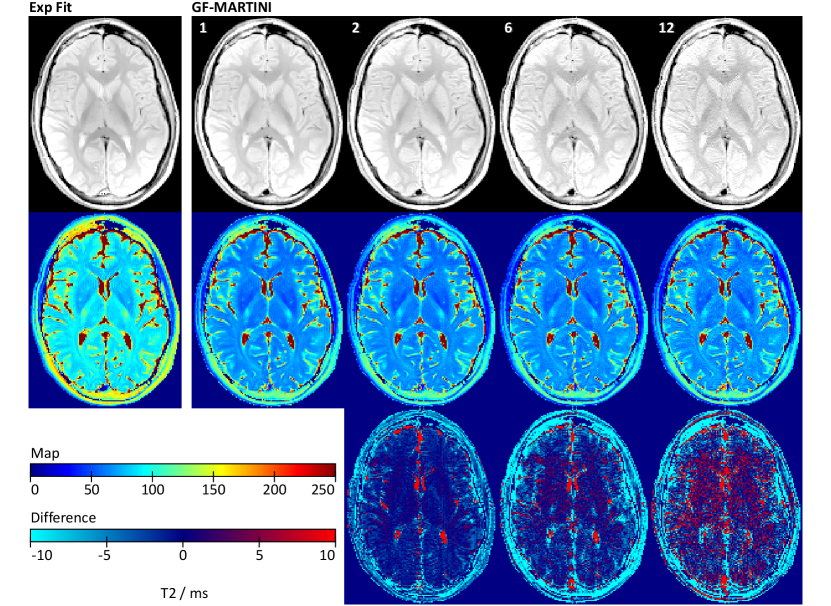

Corresponding results for a transverse section of the human brain are shown in Fig. 6.

Whereas a pixel-wise exponential fit of the fully sampled MSE data (first echo removed) again leads to a systematic T2 overestimation, the GF-MARTINI method presents with good accuracy for all undersampling factors. The most notable distortions are small vertical ghosts near the hemispheric fissure, which increase for higher undersampling factors. For the highest acceleration factor of , also the spin-density map suffers from edge enhancement and blurring. A quantitative ROI analysis of T2 values in various brain tissues is summarized in Table III.

The mean T2 values obtained by GF-MARTINI are in remarkably good agreement with the fully sampled reference and very stable for all undersampling factors. Moreover, Fig. 7

depicts reconstructions of the same data with the assumption of a constant T1 for all pixels. It turns out that the GF-MARTINI reconstructions with constant T1 are almost indistinguishable from the results obtained with a full T1 map. The ROI analysis in Table III confirms this observation as all measurable deviations between the two GF-MARTINI versions remain within .